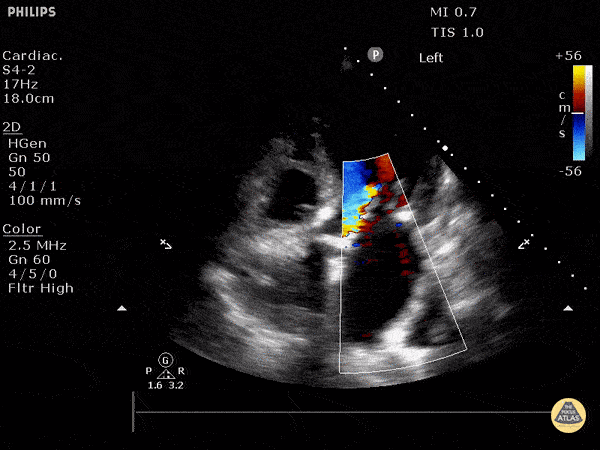

Mixed aortic and mitral regurgitation with color doppler. Justin Bowra MBBS, FACEM, CCPU Emergency Physician, RNSH et al.